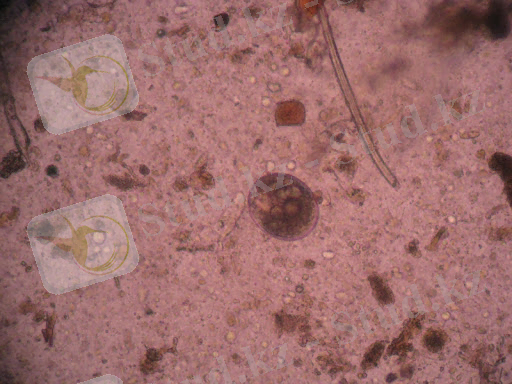

- Сурет. Балантидиоз

Шошқалардан басқа, адамдарда, ірі қара және ұсақ малдар мен қояндарда балантидиоз ауруы тіркелді.

Қоздырғыш туралы мәлімет. Aprotricha отрядына жататын Balantidium suis және E. coli. Екі түр де морфологиялық жағынан ұқсас. Балантидиялар трофозоиттер және кисталар түрінде кездеседі. Трофозоиттер сопақ немесе жұмыртқа тәрізді, ұзындығы 100-150 мкм, ені 20-70 мкм; ішінде екі ядро - макронуклеус және микронуклеус бар.

Дене кірпікшелермен жабылған, нәтижесінде балантидия шырышты қабатқа, тіпті шырышты қабық астына да ене алады. Кисталар дөңгелек пішінді, қос қабықпен жабылған, қозғалыссыз. Көбінесе кисталар ересек клиникалық сау жануарлардың нәжісінен оқшауланады. Жас жануарларда трофозоиттер (вегетативті формалар) қоршаған ортаға бөлінеді.

Нәжіс үлгілері алынады, олар 2-3 сағаттан кешіктірмей нативті жағынды әдісімен зерттеледі. Балантидия лизисі кейінірек болатындықтан, мәйіттерді -6 сағат зерттейді. Нәжіс әйнек шыныға қойылады және бірдей мөлшерде натрий хлоридінің изотоникалық жылы ерітіндісімен (температурасы 37 ° C-тан аспайды) біркелкі ұнтақталады, жабын әйнекпен жабылады және жағынды микроскоптың төмен үлкейтуімен қарайды. Оң жағдайларда балантидиялардың белсенді вегетативті формалары мен кисталары кездеседі.